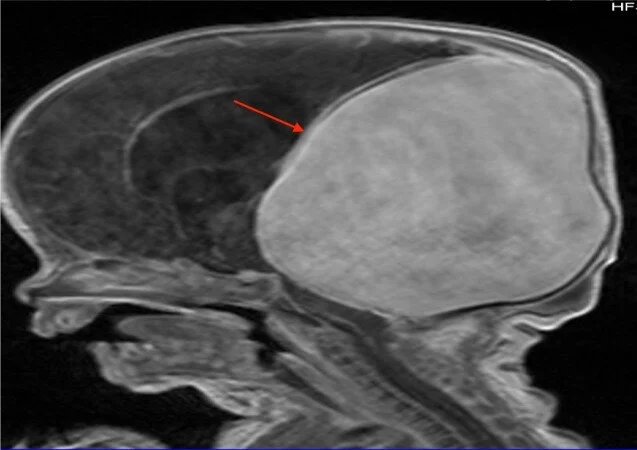

Vein of Galen aneurysmal malformation (VGAM) is a rare angiopathy, which most commonly presents in infancy. Although very rare, it is associated with high morbidity and mortality rates. In order to minimize such morbid rates, a prompt diagnosis followed by a timely initiation of management is crucial. Multiple antenatal and postnatal imaging techniques for the diagnosis have been described and discussed in the literature. However, to our knowledge, a comprehensive review exploring such a list of imaging options for VGAM has never been established. We aim to review the diagnostic tools to aid in better understanding of the investigative modalities physicians may choose from when treating patients with a VGAM.